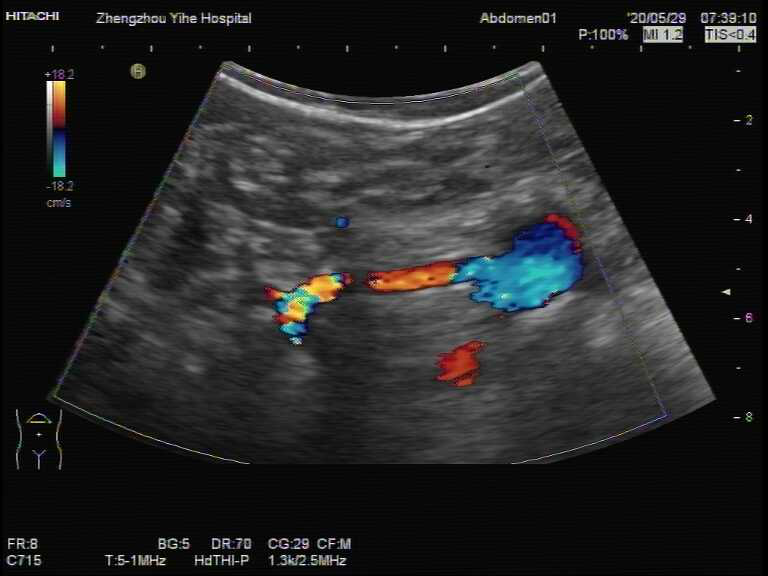

一位五十多岁男性进入诊室,这是他们单位每年例行常规来体检,彩超医生仔细认真的检查腹部各个脏器,当查至胰腺时,似乎未见明显的异常,但再仔细观察后发现胰腺的尾部后下方好像有模糊的包块。会不会是胰腺的肿块呢?彩超医生调节机器,包块逐渐清晰,是一个大小约29x23mm囊性回声。是囊肿吗?又是一个疑问!接下来医生对这个包块加个彩色多普勒,里面迅速充满了血流,哦!原来是个血管!是动脉还是静脉呢?利用频谱多普勒鉴别一下,答案马上出来:是动脉血流!(图1、2)

图1